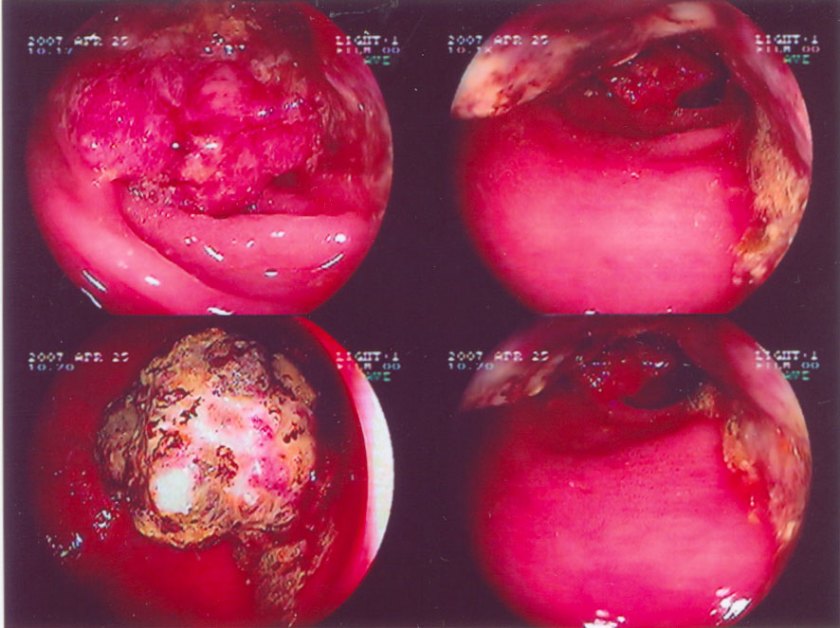

Kolonoskopi nampak fungating tumor di 12-15 cm dari ambang anal. Biopsi konfirmasi diagnosa klinis adenokarsinoma (infiltrating, focally necrotizing moderately differentiated rectal adenocarcinoma).

1. Melihat foto-foto dari dubur luka kita tahu bahwa  kanker pada Tim itu memang sangat serius.